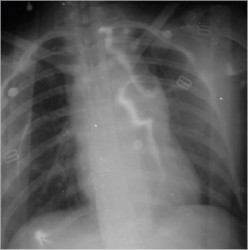

6 Comments Published by JonMikel, M.D. January 23rd, 2006 in Medical ImagesA previously healthy 17 yo woman came in to the ER because she has suffer an automovilistic accident. On the initial evaluation she was with pulse ‘parvus et tardus’ with altered mental status. A chest x-ray was ordered and found an aortic rupture.